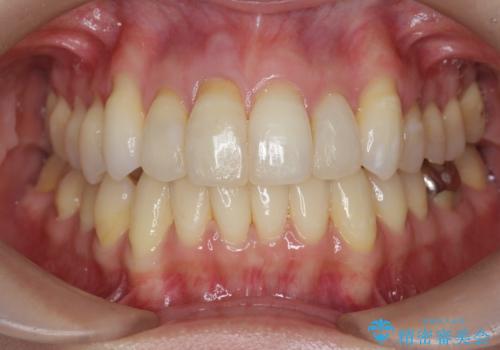

吸収し喪失した前歯、ブリッジによる審美性の回復

上顎4前歯は、根管治療の既往があり、虫歯も見られたことからブリッジによる治療で審美性の回復を行うとともに臨在歯の虫歯もセラミック治療を行っていきます。

欠損部の歯ぐきの量が足りない場合は、移植を行い歯肉を増大させることもありますが、今回は仮歯で様子を見た結清掃性・審美性に問題が出なかったので行いませんでした。